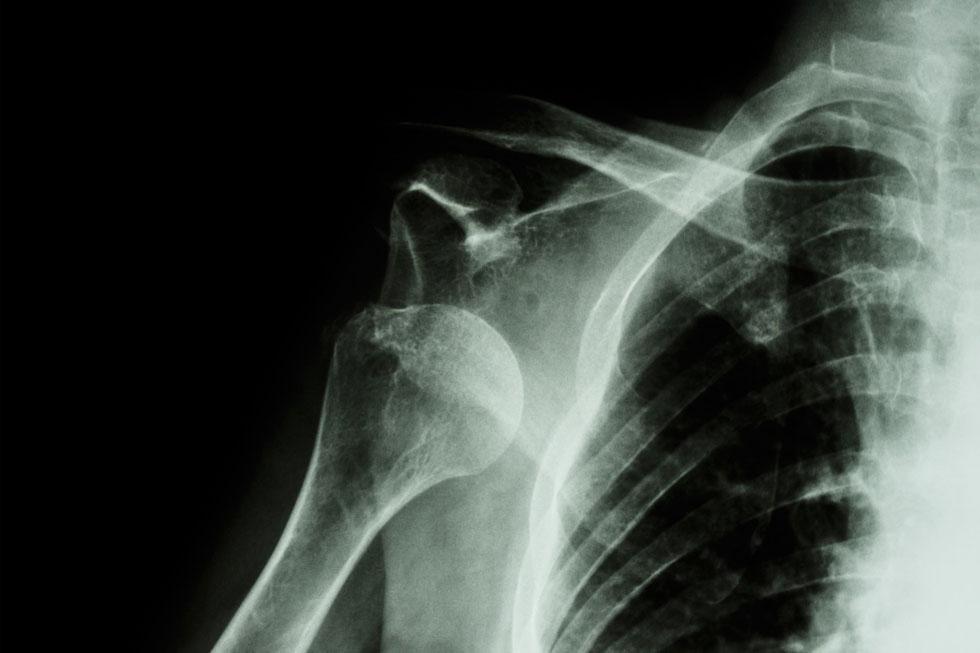

Rotator cuff tear

Shoulder dislocation

Shoulder instability

Pain during lifting or throwing